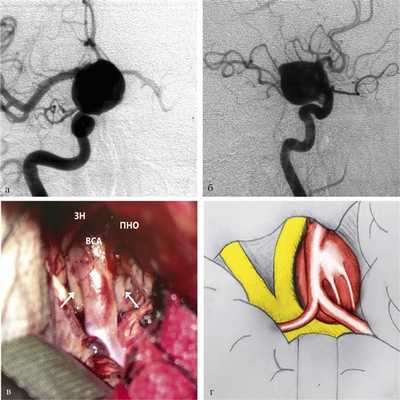

Задние (нижние) аневризмы. Задние аневризмы составили 18% от всех больших и гигантских аневризм ВСА [2]. Дно аневризм такой локализации направлено кзади, в сторону кавернозного синуса и основания средней черепной ямки. Часто аневризмы задней локализации могут иметь смешанное направление купола: в заднемедиальном или заднелатеральном направлении. Зачастую к телу крупной аневризмы ВСА задней локализации плотно прилежат ЗСА и реже ПВА, что делает их диссекцию трудоемкой. Аневризмы заднего расположения, как правило, выключаются тоннельными клипсами различной конфигурации с формированием просвета ВСА в областях фенестрации клипс (рис. 5).

Рис. 5. Параклиноидная аневризма заднего (нижнего) расположения. а — ЦАГ, прямая проекция; б — ЦАГ, боковая проекция; в — операционный вид (ЗН — зрительный нерв; ПНО — передний наклоненный отросток; ВСА — внутренняя сонная артерия; стрелками обозначено тело аневризмы); г — схема операционной картины: купол аневризмы располагается под стволом ВСА, частично смещает зрительный нерв и хиазму. ЗСА и ПВА плотно прилежат к телу аневризмы.